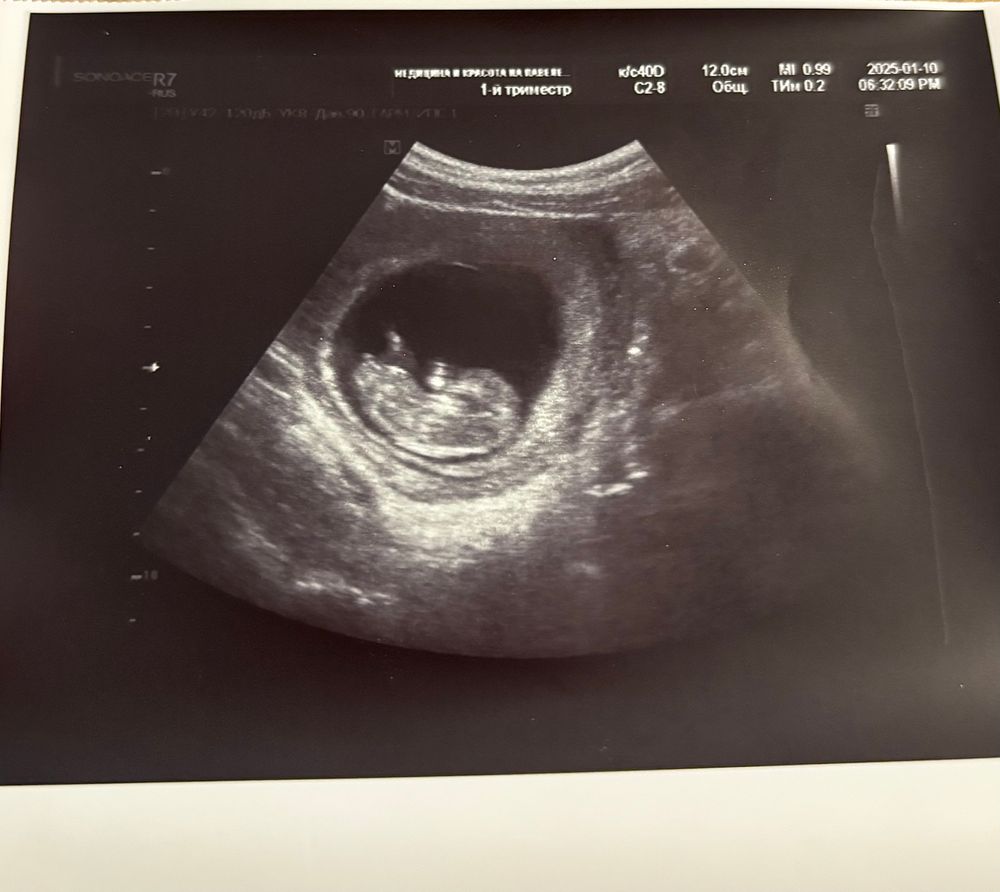

Предположу по бугорку, что девочка)

Вот и мы сейчас беременность ведем вроде бы в неплохой клинике. Срок был 10-11 недель, предположили мальчика😡😡я тоже по бугорку вижу, что больше на девочку похоже. Не знаю, может, врачи не по нему определяют. Да и не понимаю, зачем так рано говорить, если неточно( но вроде бы девочки чаще просто другой стороной располагаются, и по форме головки. Ой, сложно это все, короче 😅